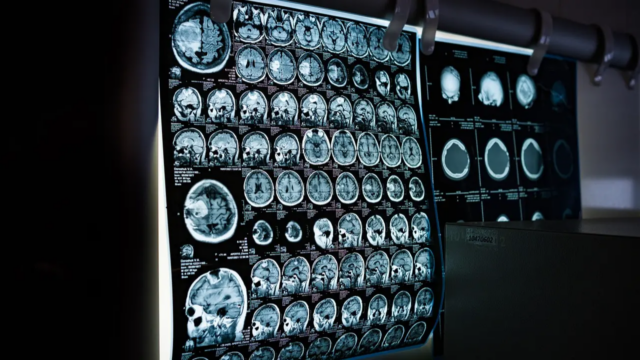

Um acidente vascular cerebral ocorre quando o suprimento de sangue para o cérebro é interrompido, causando danos às células cerebrais. A indicação crucial pode ser lembrada com SER RAPIDAMENTE – Perda de equilíbrio, problemas de visão ocular, flacidez facial, ponto fraco do braço, problemas de fala e tempo para agir prontamente.

O tratamento para acidente vascular cerebral geralmente consiste em medicamentos anti-coágulos, tratamentos de trombectomia e tratamentos de recuperação focados em restaurar a função neurológica e o estilo de vida.